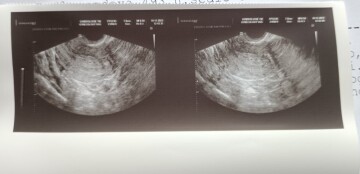

Dobrý den, předem se chci omluvit za přidání nevhodného fota. Doufám, že po Vaší odpovědi budu o něco moudřejší. Dle těhotenského testu mám potvrzené těhotenství. Dnes mi můj menstruační kalendář hlásí, že jsem 7+0d. Před kontrolou udělaný digitální test, kde podle manuálu cca 4-5 týden. Ve čtvrtek 16.11. jsem byla na kontrole, bez bolestí, vše probíhalo v pořádku. Jen do doby, kdy mi bylo řečeno, že nic nevidí. Prý to může být mladší nebo mimoděložní. Že si příroda rozhodne sama a že další týden už bude rozhodující. Mimoděložní těhotenství jsem si prodělala před dvěma lety, kdy mi byl vzatý vejcovod od té doby se nám s partnerem nepodařilo otěhotnět. Po návštěvě gynekologa jsem začala mírně špinit, ale v pátek jsem začala krvácet i se sraženinami. Opět žádné křeče ani bolest spodku. O víkendu ze mě vypadlo něco, co nedokážu definovat. Ráda bych znala Váš názor a pohled na věc, zda se může jednat o samovolný potrat. Ještě dnes mírně krvácím bez bolestí a v pátek jdu na kontrolu. Děkuji za odpověď.

Dobrý den,

vzhledem k tomu, že na ultrazvuku bych si takto dle fotky tipnula, že vidím počínající gestační váček, tak vzhledem k Vaším potížím bych to teď považovala nejspíše za samovolný potrat. Nicméně pokud bylo vysloveno podezření na mimoděložní těhotenství, tak je vhodné dosledovat dynamiku hCG. I při mimoděložním těhotenství může být v děloze patrná struktura připomínající gest. váček, nicméně v tom případě se nazývá pseudogestační váček.